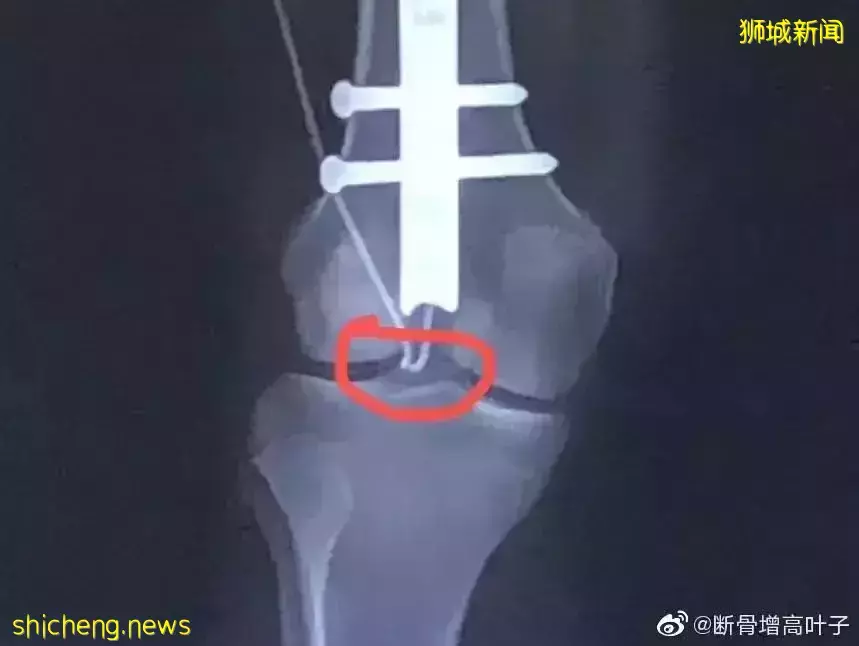

他指叶小姐的陈述失实,并指出目前叶小姐的双腿长度大致相等,骨头正在愈合, 两周前的最新X光扫描显示,两个股骨的骨缝愈合良好,植入物完整。

叶女士在术后一个星期不到右腿的线就断了,她只能再次接受手术换针。结果换针手术不到一周后,叶女士感到自己的腿部入钉处疼痛难忍,结果拍X光显示针上的钉子松了,叶女士疼的生不如死,只能第三次接受手术!

12月,叶女士接受第三次手术,第三次手术后不到一个月,针再次掉了。这时候医生才承认F针成功率只有50%。

叶女再次进行了手术,右腿两个月内开刀4次,叶女士经历的痛苦只有她自己知晓。第4次手术结果还是失败的,针已经坏了。

因为4次手术的摧残,她的右腿已经不能再进行手术了,而左腿的针正常运行,右腿不能延长,至今三个月不能弯曲,两条腿变成了长短腿。